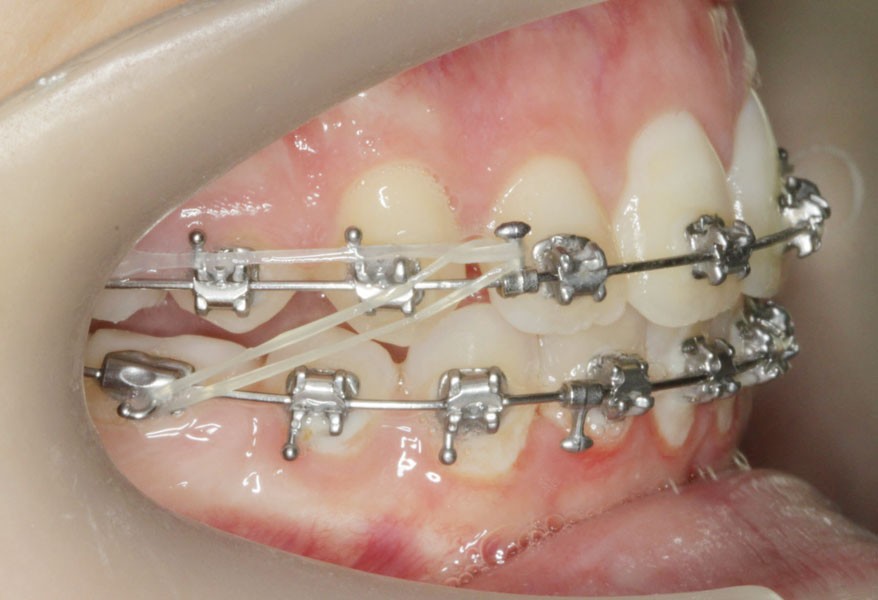

Le site des extractions s’est porté sur les secondes prémolaires. La justification de ces extractions passent par la résolution de l’encombrement sans effondrer le prémaxillaire.

La résolution de la classe II squelettique n’est aucunement recherchée au travers des extractions mais par une mécanique interarcade.

Ce cas a été conjointement suivi par les Drs Le Gall, Bachet et Dameron.